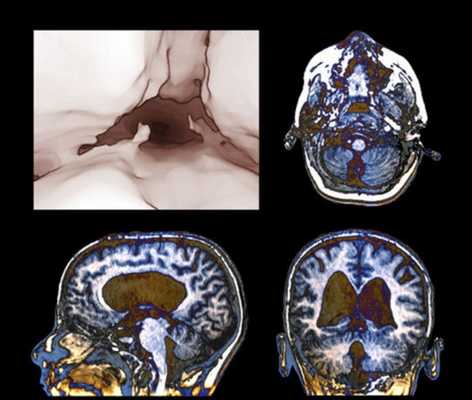

Состояние после оперативного вмешательства: эндоскопической трицистерновентрикулостомии.

При проведении МРТ головного мозга не прослеживается ток ликвора на уровне водопровода мозга, отмечается ток на краниовертебральном уровне и базальных цистернах. На уровне стомы в дне третьего желудочка - ток ликвора интенсивный.

Внутренняя тривентрикулярная окклюзионная гидроцефалия на МРТ во фронтальной и сагиттальной плоскостях: на левом снимке видно гигантское кистозно-солидное образование, явившееся причиной обструкции ликворопроводящих путей на уровне Сильвиева водопровода

Водянка головного мозга при МР-сканировании в коронарной проекции

Проявления патологии на снимках бывают прямыми и косвенными. Первые связаны с расширением желудочков мозга (III, IV и боковых (в начальном периоде — в области передних рогов и тела)), водопровода и/или субарахноидального пространства (конвекситально, в области базальных цистерн, Сильвиевых борозд и пр.). Косвенные признаки на МР-сканах:

- межжелудочковый индекс свыше 0,5;

- перивентрикулярный отек при напряженной водянке;

- смещение гипоталамуса вниз;

- локальное выпячивание крыши боковых желудочков и др.